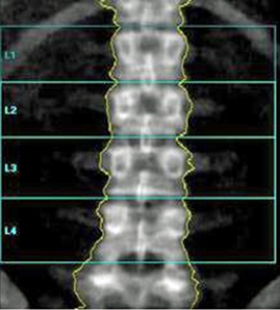

Which of the following imaging techniques illustrated in the pictures would be the most efficient to discover if there is a nerve root compression at the L4 level?

Q16: Which of the following imaging techniques illustrated

Q17: Which of the following imaging techniques illustrated